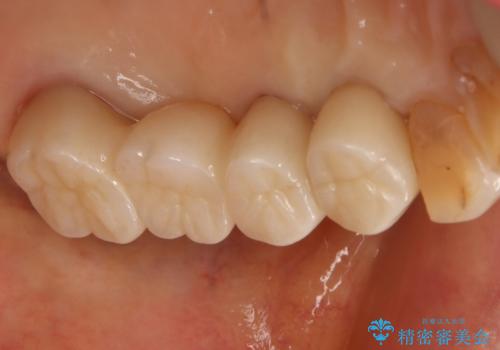

古い被せ物を除去し、中の状態をキレイにしたうえで改めて金属を使用していない被せ物で噛み合わせの回復を行いました。

被せ物の色は噛み合う反対側の被せ物と合わせて作りました。

金属を一切使わずセラミックのみで構成されており、自然な色調を再現することに長けた被せ物をオールセラミッククラウンといいます。

以前は耐久度(割れにくさ)の点で不安があるといわれていましたが、人工ダイアモンドとも呼ばれる『ジルコニア』の加工技術が向上してきたことにより、より精密で高強度の被せ物が製作されるようになりました。

ジルコニアで補強したベースの上に細かな色調が再現できる陶材を築盛することで周りの歯と調和した色調の被せ物の作製が可能となっています。